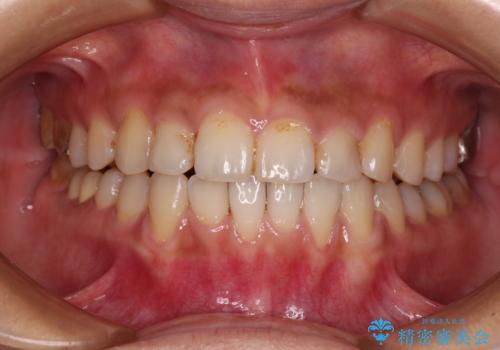

前歯のデコボコとクロスバイト インビザラインによる矯正治療

- 上下のクロスバイトと前歯のデコボコを気にして来院された患者様です。

骨格的に下顎がやや前方にあり、奥歯にクラウンが装着されているため、矯正治療後半の不安定な咬み合わせを避けるのであればワイヤー矯正がおすすめとなりますが、希望によりインビザラインにて治療を行うこととしました。

インビザラインを用い、IPR(歯と歯の間を削る)と歯列全体を拡大させることで、歯並びを整えていくこととしました。

懸念されたとおり、右下のクラウン部分が全く咬み合わず、仕上げの段階で治療期間が長くなりました。